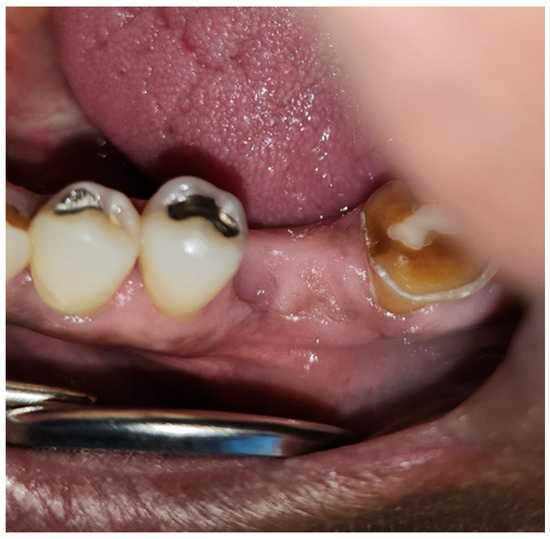

| 1 | M | 69 | Squamous cell carcinoma | Base of Tongue (Oropharynx) | 70 Gy/(Yes) | Mandibular First Molar (#19) | High | Complete Healing |

| 2 | M | 70 | Squamous cell carcinoma | Ventral Tongue/Floor of Mouth (Oral Cavity) [Right] | 70 Gy/(Yes) | Mandibular Incisors and First Molar (#24, #25, #26, and #30) | High | Complete Healing |

| 3 | F | 59 | Squamous cell carcinoma | Tonsil (Oropharynx) [Right] | 70 Gy/(Yes) | Mandibular First Molar (#19) | Moderate | Complete Healing |

| 4 | M | 75 | Adenoid cystic carcinoma | Hard palate/Maxillary Sinus (Oral Cavity) [Left] | 66 Gy/(No) | Mandibular Second Molars (#18 and #31) | Moderate | Complete Healing |